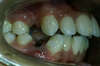

Vues avant le traitement